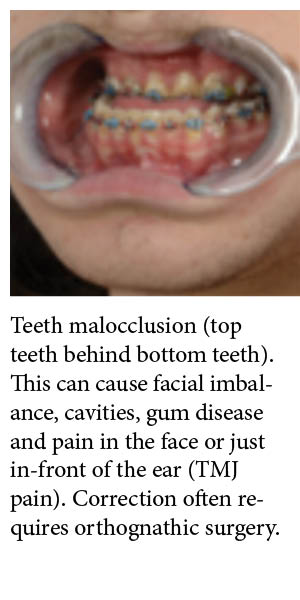

Jaw Dysfunction

Dysfunction of the upper and/or lower jaws has a variety of causes including temporomandibular joint (TMJ) dysfunction, congenital dento-facial abnormalities and issues that arise after treatment of trauma, cancer or other pathologies.

Jaw dysfunction can be accompanied by abnormal alignment of the teeth, or malocclusion, which can result in facial imbalance, cavities, gum disease and pain in the face or just in-front of the ear (TMJ pain). Jaw dysfunction can also result in poor self-esteem and anxiety around the overall appearance of the face jaw dysfunction can often be treated with orthognathic surgery.

Image 2: Teeth malocclusion (top teeth behind bottom teeth). This can cause facial imbalance, cavities, gum disease and pain in the face or just in-front of the ear (TMJ pain). Correction often requires orthognathic surgery. |